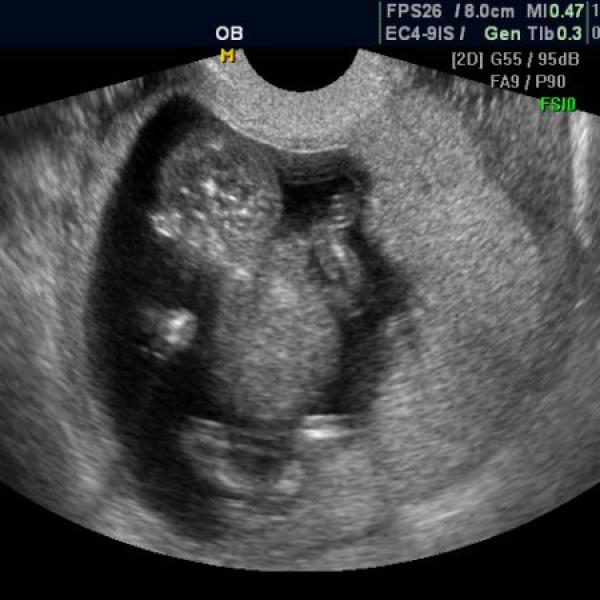

+ ještě přikládám utz ze 10tt